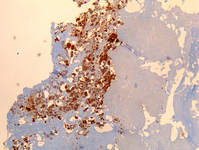

Endocardite por Coxiella burnetii: imuno-histoquímica. Observe o baixo nível de inflamação. A coloração marrom identifica bactérias em monócitos/macrófagos dentro. Geralmente a vegetação está ausente

Hubert Lepidi, Institut Hospitalo-Universitaire Méditerranée Infection